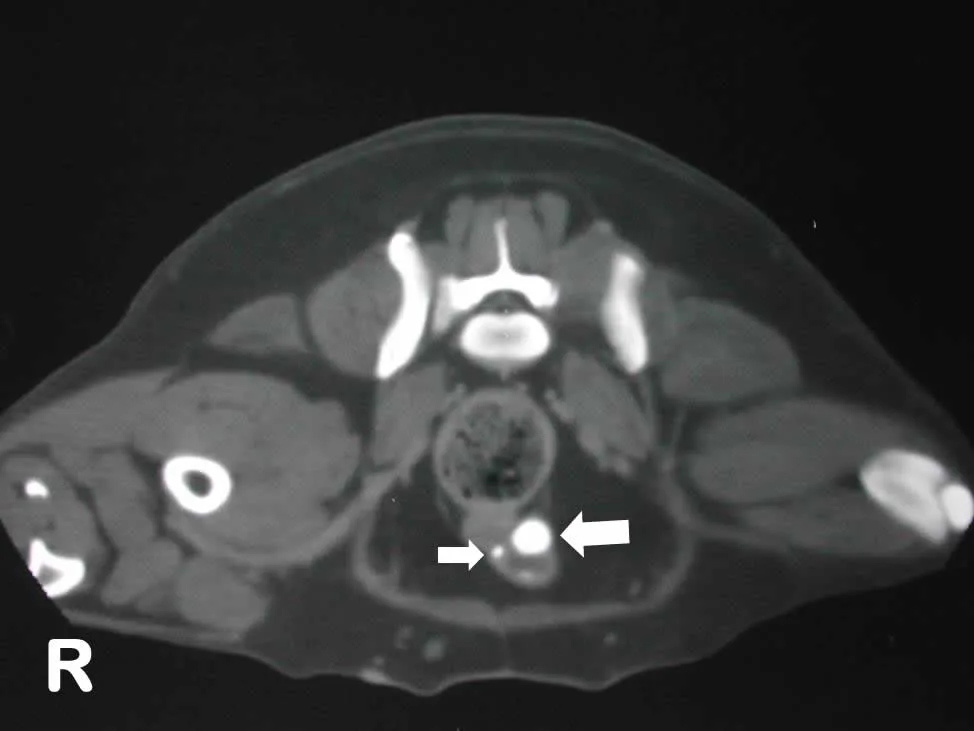

Contrast-Enhanced Computed Tomography (CT)

This is the best diagnostic imaging modality for the diagnosis of EU (Figure 2). Shown are the dilated EU (large arrow) and nondilated EU (smaller arrow), both within the urethral wall.